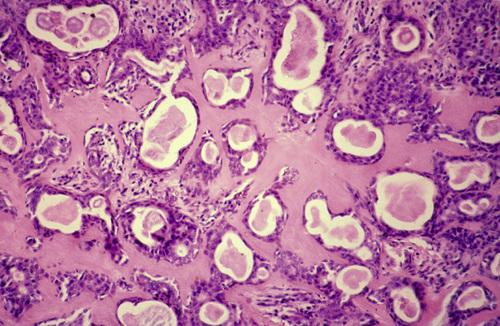

Low-power view showing a papillary cystic tumor with a lymphoid stroma. The epithelium is oncocytic, forming uniform rows of cells surrounding cystic spaces.

Warthin tumor

High-power view of epithelial lining showing double row of oncocytes with adjacent lymphoid stroma. The inner luminal layer consists of tall columnar cells with centrally placed, palisaded, and slightly hyperchromatic nuclei. Beneath this is a second layer of cuboidal or polygonal cells with more vesicular nuclei.

Warthin tumor